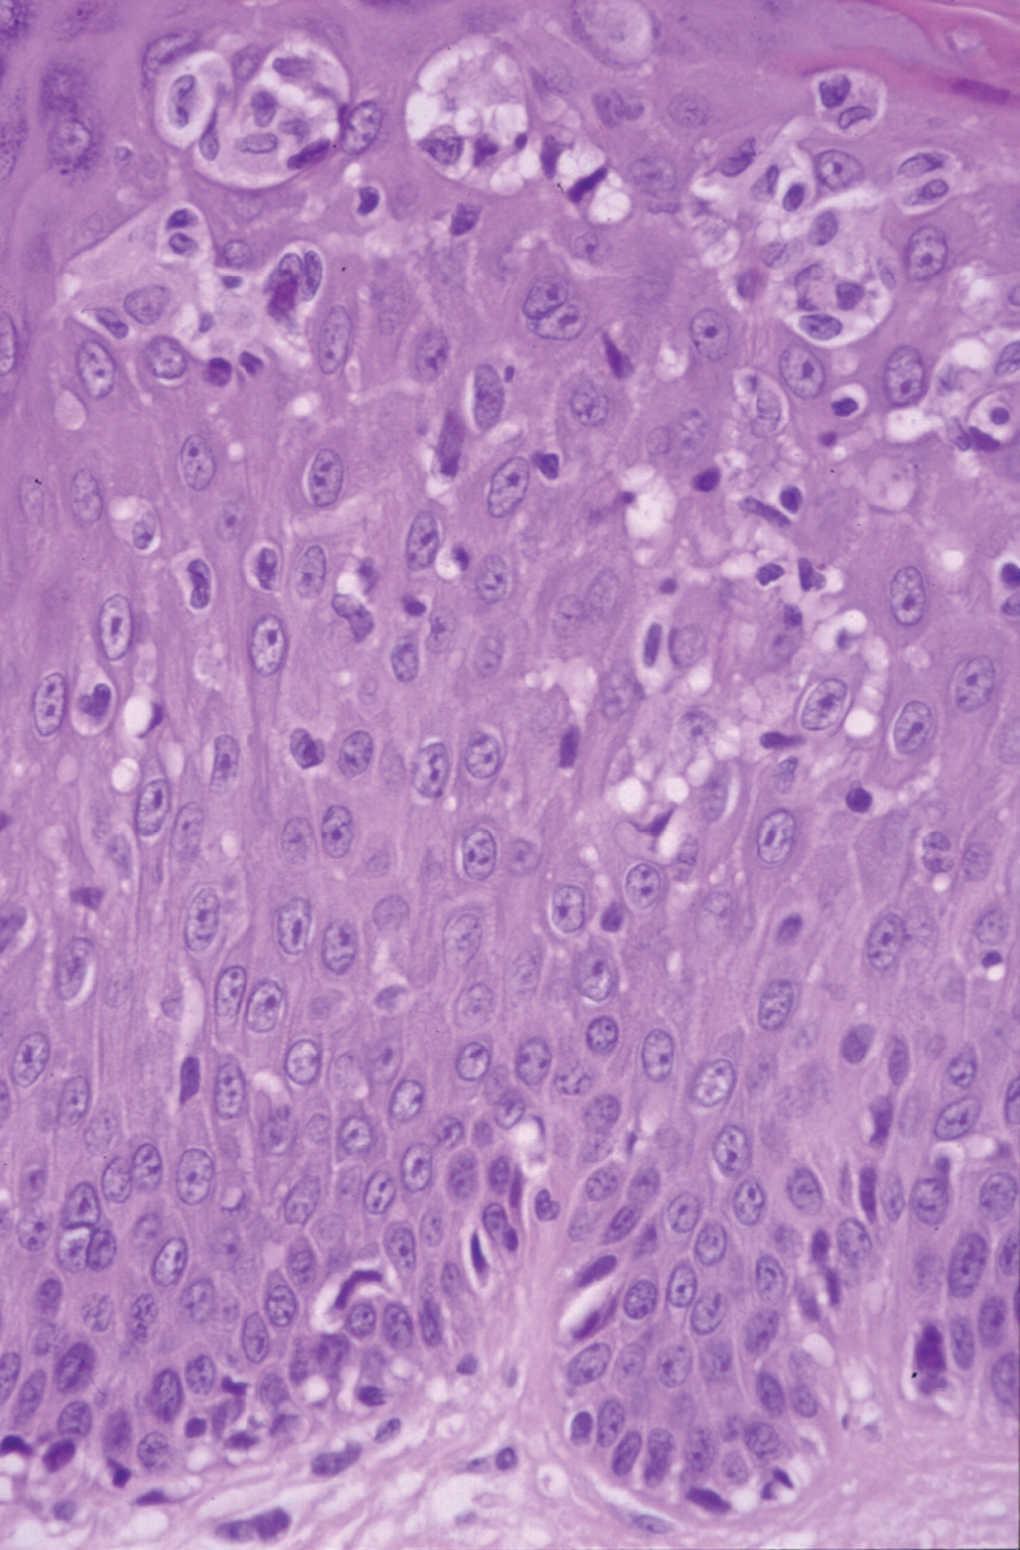

Fig. 4.--Caso 2. Epidermotropismo de linfocitos atípicos de pequeño tamaño y microabscesos simulando una micosis fungoide. (Hematoxilina-eosina, x400.)

Nuestros pacientes tenían como hecho en común el patrón histológico tipo micosis fungoide. En el primer caso existía un denso infiltrado en banda de linfocitos pequeños en la dermis superficial con un epidermotropismo focal. Sin embargo, tanto en el segundo como en el tercer caso, se apreciaba mayor epidermotropismo con linfocitos atípicos de mayor tamaño y núcleo irregular que histológicamente recuerdan a la micosis fungoide.

Recientemente se ha realizado un estudio clinicopatológico y genotípico en 8 casos de seudolinfomas inducidos por anticonvulsivos 13. Las similitudes entre los seudolinfomas y las micosis fungoides fueron el epidermotropismo de linfocitos atípicos (100 %) y los microabscesos de Pautrier en el 38 %. Sin embargo, como hecho diferenciador en los seudolinfomas, existe una espongiosis que puede ser desde moderada a marcada (75 %), queratinocitos necróticos (63 %), infiltración de eosinófilos en la epidermis (25 %), edema de la dermis papilar (100 %), eritrocitos extravasados (100 %), linfocitos en la dermis mayores que aquellos que están en la epidermis (63 %) e infiltración de varias células inflamatorias incluyendo neutrófilos (50 %).